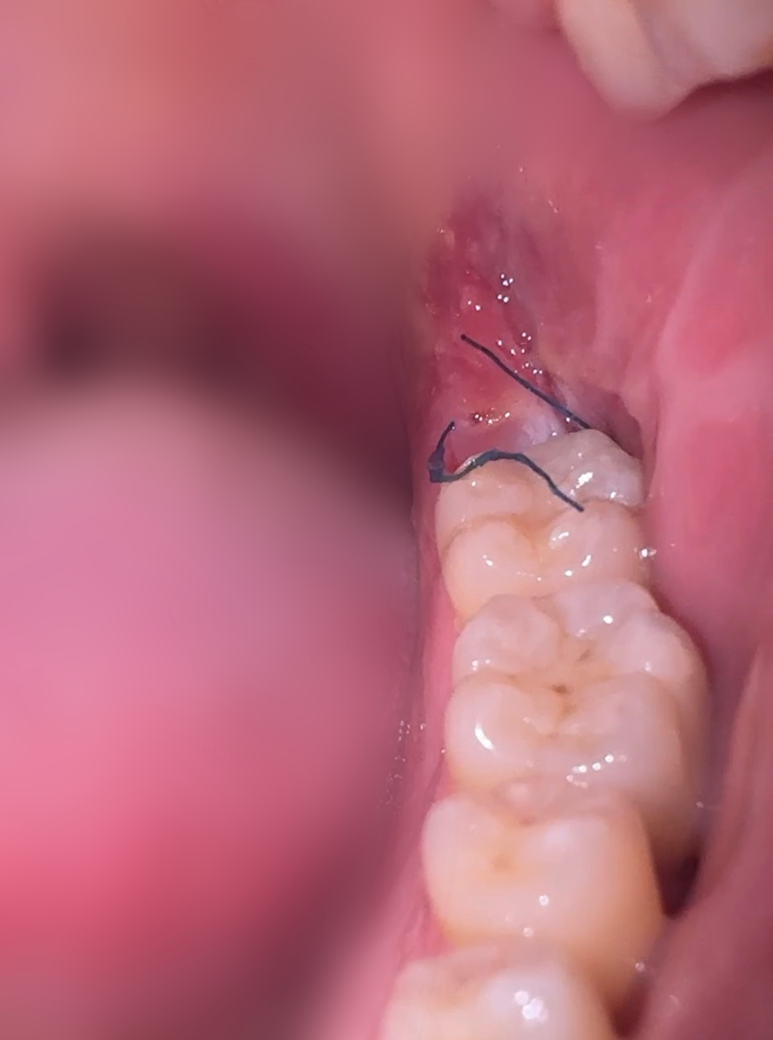

사랑니 발치 후 다음날부터 실밥이 이정도로 풀렸는데

신경안써도되나요 ?

혈병이란게 뭔지 보이지도않아서 잘되고있는건지도 모르겠고

사진에서 정상적으로 아물고 있습니다. 실밥은 떨어져 나가도 문제되지 않습니다. 1주일 후에 남은 실밥 풀면 됩니다.

실밥이 풀릴수도 있습니다. 사진상을 보면 잇몸이 잘 아물고 잇으니 걱정은 안하셔도 될것같습니다. 실밥이 불편하시면 치과에 가셔서 제거나 소독을 한번 받아보시면될것같습니다.

현재사진만으로는 정확히 발치부위가 보이지 않습니다

봉합은 어느정도 풀려버린 것 같은데 양치질하다가 자연스럽게 실밥은 빠져나올 가능성이 높습니다